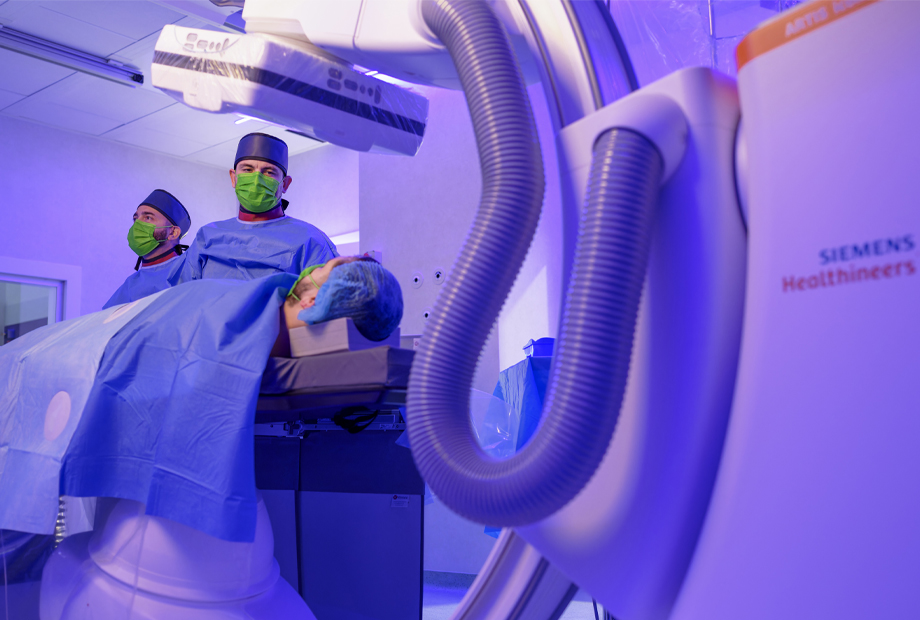

Rotablația: tratament avansat pentru artere coronare calcificate, la pacient de 80 de ani, cu afecțiuni complexe